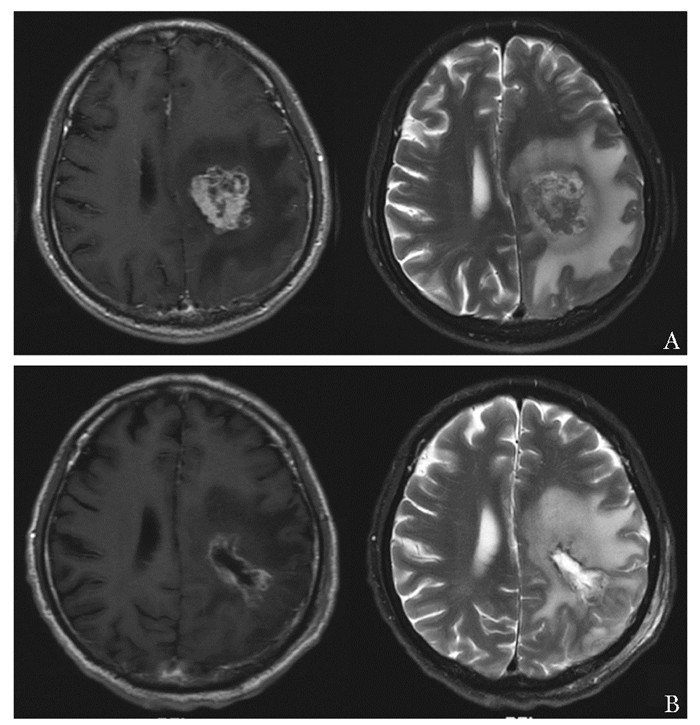

• 摘要: 肾细胞癌是泌尿系统中恶性度较高的肿瘤,常出现远端转移,尤其伴随中枢神经系统转移后,患者预后更差,临床管理困难,需多学科协作诊疗。本文报道一例肾透明细胞癌多系统转移患者,经北京协和医院肿瘤多学科协作团队(multidisciplinary team,MDT)5次会诊,得到个体化诊疗,并取得良好效果。通过对MDT讨论决策进行详细分析,可展现MDT在疑难重症病例诊疗方面的优势,有助于缩短治疗时间窗、打破科室界限、提高患者依从性、更好地制定符合循证医学理念的诊疗建议,为患者提供更加精准、个体化的临床管理方案。

Abstract: Renal cell carcinoma(RCC) is a type of tumor with a high degree of malignancy in the urological system, often with distal metastases, especially to the central nervous system. These patients are often endowed with poorer prognosis and more complex management that require a multidisciplinary team(MDT). This article reported a case of clear cell renal cell carcinoma with multisystem metastases.The MDT of Peking Union Medical College Hospital(PUMCH) discussed and formulated the optimal individualized treatment scheme for the patient, and achieved good results after 5 consultations. Through a detailed analysis of discussions and decisions of MDT, the advantages in the treatment of such difficult and serious cases are demonstrated, including shortening the time window of treatment, breaking down departmental boundaries, improving patients' compliance, developing treatment recommendations in line with the concept of evidence-based medicine, and providing more accurate and individualized clinical managements for patients.